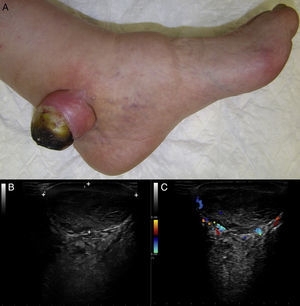

Varón de 89 años, sin antecedentes personales de interés, que consultó por una lesión asintomática en talón izquierdo de 40 años de evolución, que se había ulcerado en los últimos meses. Presentaba una tumoración indurada sésil de 3,5×4cm, color piel normal, con costra amarillo-marronácea exudativa superficial (fig. 1A). La ecografía cutánea (sonda lineal 18MHz) mostró una lesión hipodérmica que descansaba sobre la fascia, bien delimitada, heterogénea, con aspecto seudotesticular, y tractos lineales hiperecoicos en su interior (fig. 1B). El modo Doppler evidenció la existencia de vascularización periférica (fig. 1C). Se realizó la exéresis completa de la lesión, estableciéndose mediante estudio histológico el diagnóstico de schwannoma anciano.

El schwannoma anciano es una variante infrecuente del schwannoma. Son lesiones sólidas, encapsuladas, de crecimiento lento y larga evolución, cuya característica principal es la presencia de cambios degenerativos en la histología. Desde el punto de vista ecográfico, el schwannoma anciano se muestra como una lesión de localización y vascularización variable, bien definida, que asocia en su espesor áreas quísticas hipoecoicas, hemorragias y calcificaciones hiperecoicas, estructuras cordonales hiperecoicas fasciculares y/o colecciones líquidas anecoicas. La transformación maligna es excepcional, sin embargo, no es infrecuente que esta sea sospechada inicialmente, debido a sus características clínicas e histológicas.